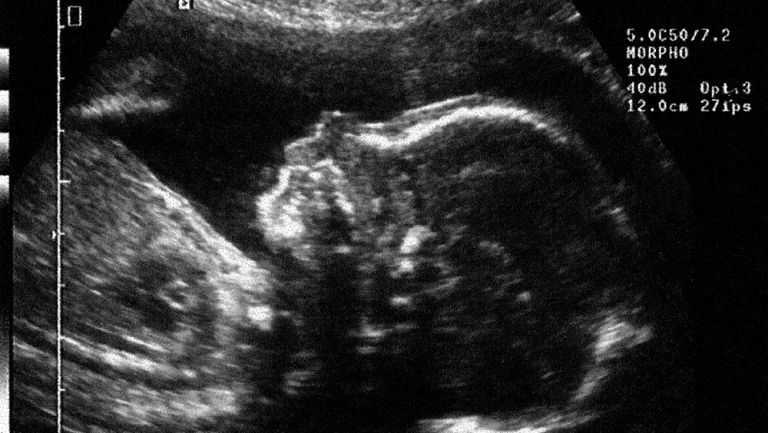

وأوضحت نجاح زرع إحدى البويضات الخمسة التي تم تشكيلها داخل رحم المريضة؛ لتنجب طفلا يدعى "جول" في يوليو/تموز، مضيفا أنه يتمتع بصحة جيدة الآن ويبلغ من العمر 7 أشهر.